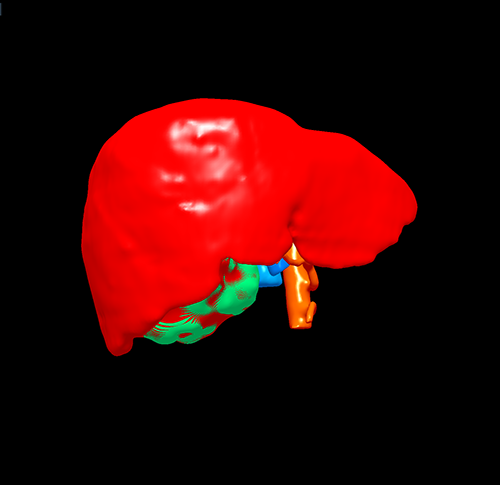

右肝癌----S567切除